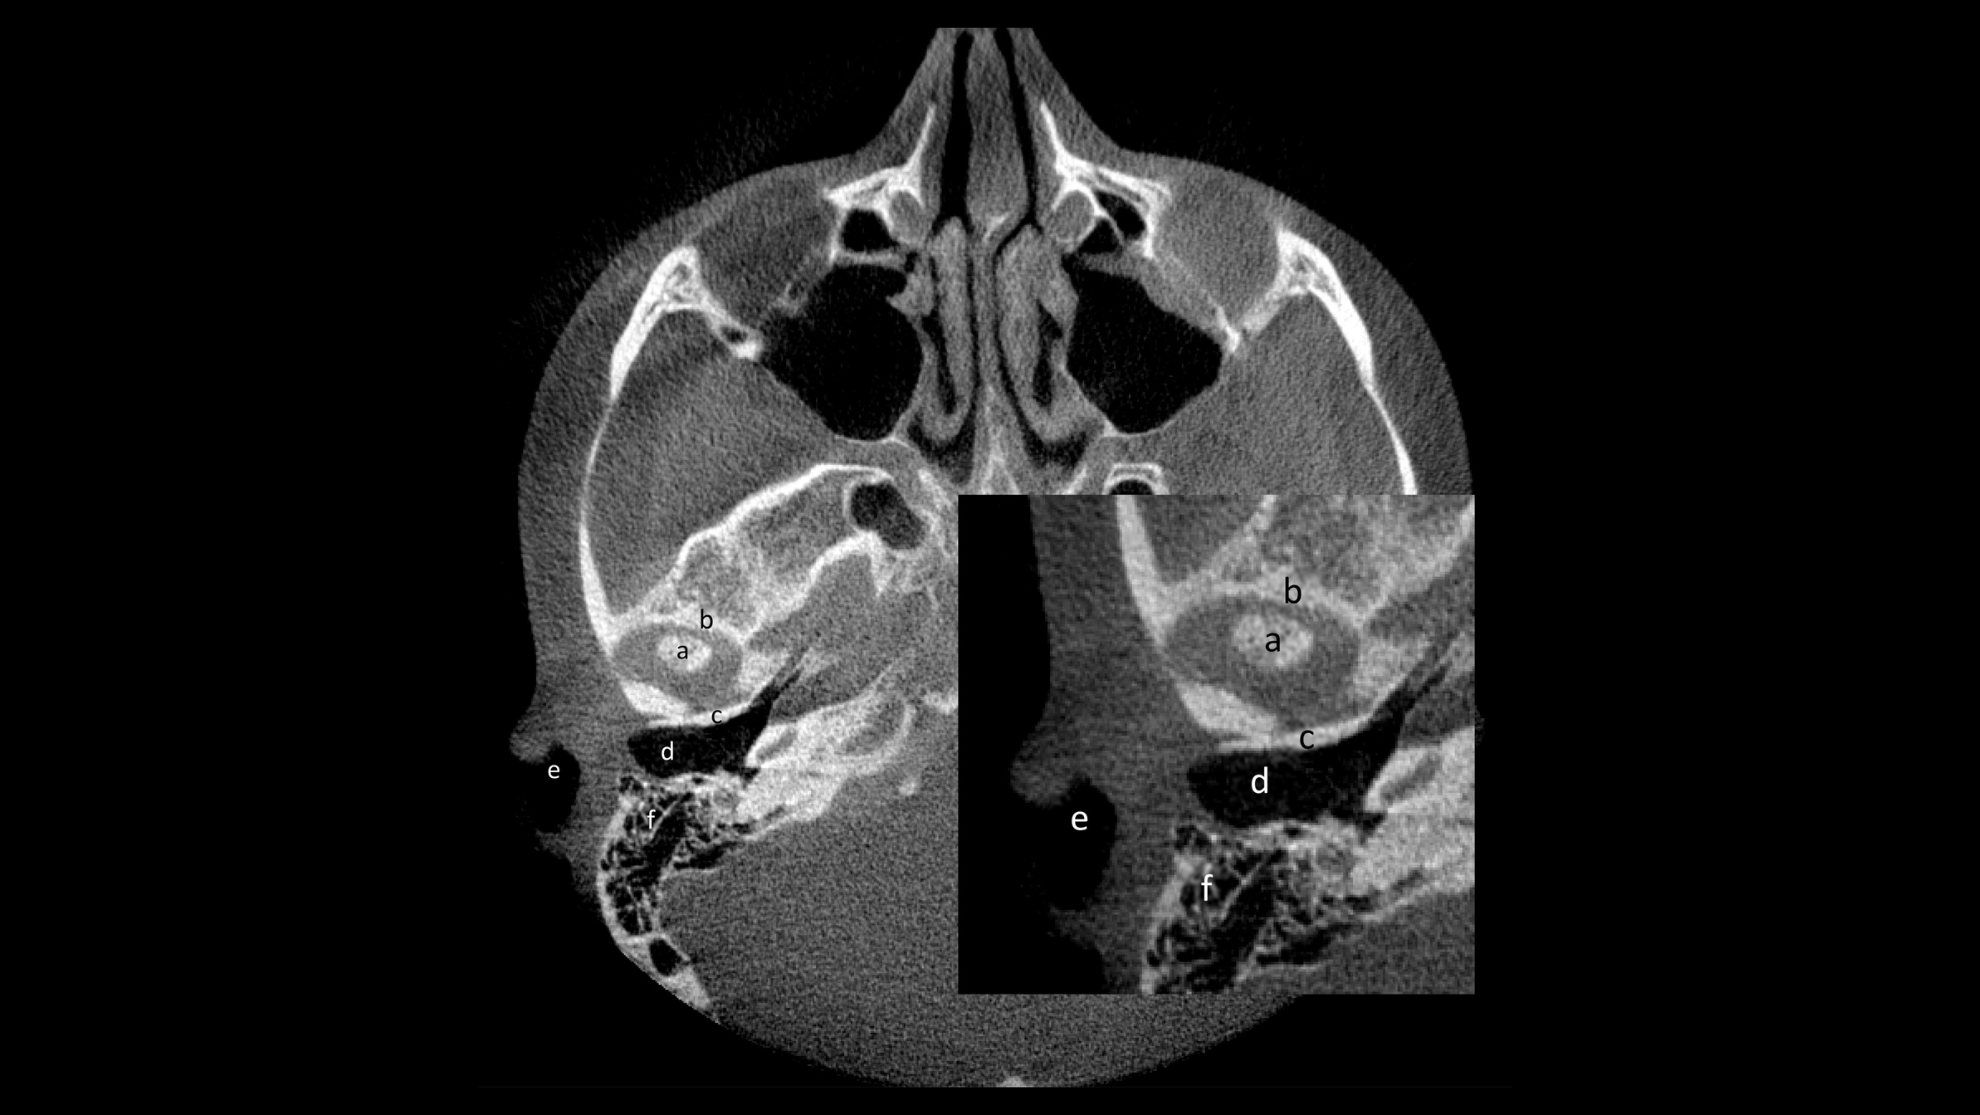

Imaxe ilustrativa da rexión de interese (ROI, polas siglas en inglés) nun corte axial de CBCT. Descrición radiolóxica das partes anatómicas da articulación: (a) cóndilo mandibular da ATM, (b) apófise preglenoidea (óso temporal), (c) apófise postglenoidea (óso temporal). Áreas anatómicas utilizadas para identificar a ATM nun corte axial: (d) trompa de Eustaquio, (e) conduto auditivo externo, (f) apófise mastoides.

Persoal investigador da USC, IDIS, e CHUS, en colaboración co de institucións de Dinamarca e Suíza, sérvese de tomografías computerizadas para detectar e medir o engrosamento do líquido sinovial na articulación temporomandibular

Se ben noutras articulacións como os xeonllos se desenvolveron métodos para medir o volume do revestimento sinovial na sinovite crónica a través de RM reforzada con contraste, estes nunca se aplicaran á articulación temporomandibular , cuxa valoración clínica é moi diferente da das outras articulacións. Agora, a colaboración entre persoal investigador da USC, o IDIS, o CHUS e as citadas institucións de Dinamarca e Suíza, permitiu idear un novo método co que calcular volume articular e ofrecer unha medida cuantitativa indirecta do tecido inflamado na ATM. No estudo, que acaba de ser publicado na revista Orthodontics and Craniofacial Research, pártese da accesibilidade e o fácil manexo dunha proba radiográfica como a tomografía computerizada de feixe cónico (CBCT polas súas siglas en inglés), unha técnica de uso habitual nas clínicas dentais, para aproveitala no exame clínico destas pequenas articulacións con artrite. Segundo as autoras e autores, isto permite confirmar a presenza de líquido inflamatorio nesa articulación tan pequena por un aumento do volume. A través deste novo método, que calcula o volume articular a través de demarcacións de áreas, o persoal investigador detectou unha alta diferenza entre doentes con AIX e as persoas sas que conformaron o grupo de control. O volume resultante na ATM de doentes con artrite foi o dobre que na articulación de individuos sans.

No estudo, a estimación do volume articular en ATMs afectadas pola AIX logrouse perfilando o espazo articular inflamado en imaxes de CBCT. Deste xeito, o equipo investigador establece un criterio para a identificación da AIX, definido por un cuadrante onde non se atopa ningunha das persoas con esa doenza. O interese clínico desta delimitación numérica, que expande así o abano de posibilidades de diagnose con ferramentas de imaxe, estriba no feito de que abre a porta a identificar a existencia de artrite na ATM en casos dubidosos cunha técnica de baixo impacto comparada coas ata o de agora existentes.